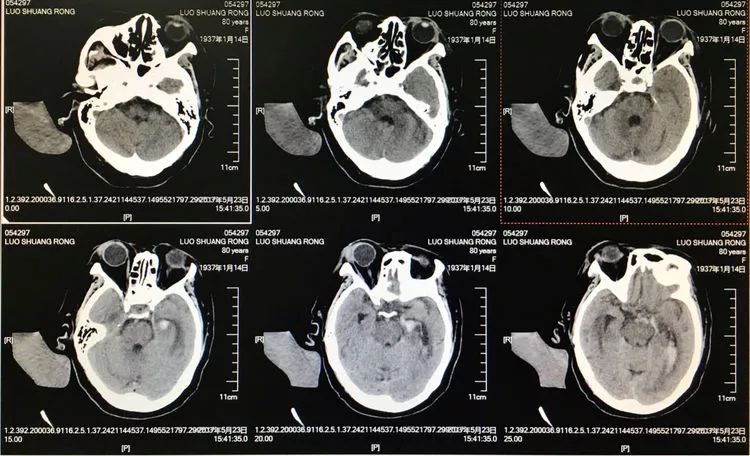

患者女性,80岁,以SAH于2017.5.20急诊入院,CTA示基底动脉顶端动脉瘤。

回到工作位造影,显示基底动脉顶端动脉瘤完全栓塞,基底动脉顶端四根血管畅通。

术后左椎动脉正位、侧位的造影和蒙片